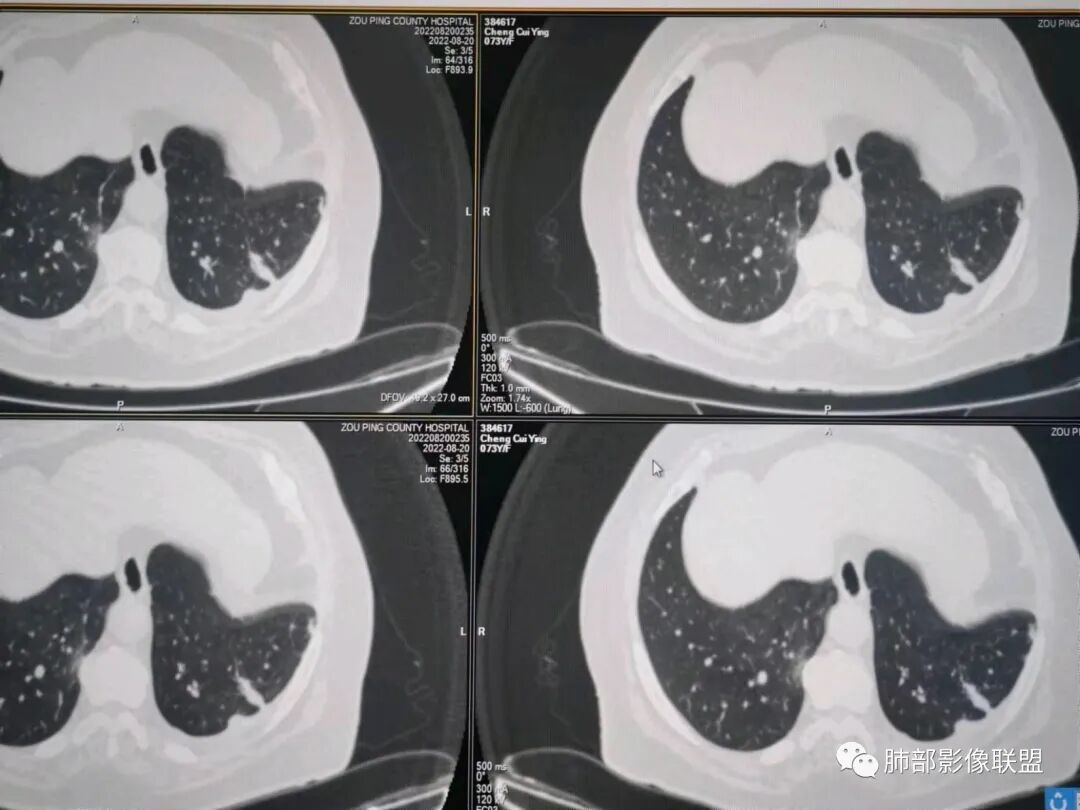

秦化君:左肺下叶外基底段胸膜下软组织密度结节性,边缘毛糙与血管相连,密度不均,增强后病灶内边界不清低密度区,胸膜栽桩,少量胸腔积液。考虑恶性病变,腺癌可能。真菌待排。

谢加平:老年女性,慢性咳嗽,咳白痰史,左肺下叶后基底段胸膜下肿块,类圆形,边界清膨隆,密度不均匀,低强化及小灶性坏死,坏死轮廊不清,胸膜下栽赃明显,左侧胸腔少量积液,向胸壁肌侵犯,另肿块近心侧见支指套征,粘液低密度,支持恶性,粘液腺Ca,经皮肺穿刺活检明确诊断。

361度:老年女性,发热,胸部CT示左下肺胸膜下结节影,血管集束,毛棘,密度不均,胸膜栽赃,少量胸腔积液,不均匀强化,坏死边界不清,肿标轻微升高,考虑恶性,鳞癌合并感染。

红星:老年女性患者。胸膜下结节病变,明显的膨胀,并局部侵犯胸膜,增强明显的强化。病灶周围带有局灶的渗出性改变以及条索上的影。考虑腺癌的可能性大,鉴别结核肉芽肿性病变。

春秋:左肺下叶胸膜下结节,边缘平直,内见低密度区,胸膜下胸腔积液相隔,考虑炎性结节可能性大,伴小脓肿形成。

宇宙:左肺下叶胸膜下球形肿块,边界尚清,局部平直,局部膨隆,内侧缘长索条,胸膜栽赃,轻度不均匀强化,其内坏死边界欠清,左侧胸水,考虑腺癌,鉴别放线菌。

党医生:左下肺结节,整体呈不完全规则、局部呈球形结节,有较长、轻大的条索壮改变,球形病变区域与胸膜呈宽基底,密度不均匀、有液化低密度区,不均匀强化,总体分析考虑:结核可能大,其次炎性假瘤,肺癌可能小。

摘星空竹子:左肺下叶后基底段与外基底段交界处胸膜下椭圆形软组织肿块,边界尚清,密度欠均匀,患侧少量胸腔积液,增强扫描轻度或无强化,肿块中央可见斑片状低密度区,边界尚清,考虑OP伴脓肿或结核,鉴别腺癌。

李庆东:左肺下叶外基底段胸膜下球形软组织密度,边缘毛糙与血管相连,轻度强化,增强后病灶内边界不清低密度区,宽基底于胸膜,少量胸腔积液。考虑良性病变,炎性假瘤可能大。特殊感染待排,鉴别腺癌。

袁媛:左肺下叶胸膜下球形肿块,宽基底连于胸膜下,胸膜栽赃,边缘膨隆,有血管供应,增强有强化,考虑腺癌。

gaoql:倾向肿瘤,胸膜下脂肪间隙受累,有细角和nse升高,如果男性,要考虑鳞癌,但是个女性,还是先考虑腺癌的可能。感染指标升高,还需鉴别炎性肉芽肿性病变,能累及胸膜下间隙的,要鉴别脓肿或放线菌。

看图说话:胸膜下肿块,密度不均,边缘毛糙,增强后不均匀强化,胸膜栽赃,左侧胸腔积液,腺癌,鉴别肉芽肿。

songml:老年女性,反复咳嗽咳痰胸闷4年,加重伴发热一周。左肺下叶后基底段胸膜下肿块影,密度较均匀,边缘较清,侵及胸膜下脂肪间隙。考虑恶性病变,腺癌可能,鉴别真菌感染。

人生海海:左肺下叶不规则形软组织密度影,膨隆生长,边缘清楚,分叶,棘突征,支气管截断,血管纠集,病灶轻度强化、内多发坏死,左侧少量胸腔积液,考虑粘液腺癌,鉴别肺脓肿。

位移:老年女性,左肺下叶肺胸膜下团块影,边界清、毛糙,膨隆,内密度不均,不均匀强化,内见坏死,胸膜栽赃,胸腔少量积液,首先考虑恶性肿瘤,低分化腺癌,鉴别小细胞癌,炎性假瘤。

赖晓宇:膨隆,浅分叶,支气管截断,内部坏死边界不清,胸膜受累,胸腔积液,考虑恶性。

枷黎:左肺底类圆形结节,略分叶,毛刺不明显,周围似乎有淡淡的晕,增强扫描呈较均匀轻度强化。结合临床症状和实验室检查,首先考虑炎性肉芽肿类病变可能,肿瘤待排。

赵:增强病变与胸膜分界清晰,平扫密度左侧胸腔密度高能否是慢性炎症刺激引起,坏死边缘清晰,提示病变强化明显。临床实验室检查血象增高先考虑慢性炎症,腺癌待除外。

许慧良:老年女性患者,左肺下叶后基底段胸膜下结节影,边界清楚,密度不均匀,内部有低密度影,边缘有结节颗粒感,对胸膜有黏连牵拉感,考虑恶性,腺癌可能。

王静:左肺下叶病变,紧贴胸膜,楔形,尖端朝向肺门,临近胸膜未见明显增厚,胸腔少量积液,增强扫描病变内部不均匀强化,可见边界相对清晰液化坏死区。患者有发热病史,血象高。诊断,左肺下叶炎性肌纤维母细胞瘤可能,鉴别肉芽肿性病变。

梦妮6-1:老年女性,慢性咳嗽,咳白痰史,左肺下叶后基底段胸膜下肿块,类圆形,边界清膨隆,密度不均匀,中间有低强化及小灶性坏死,边界清,有胸水,病肺门侧有支管通过,胸膜界线清,考虑良性病可能。隐球菌?

WXD:左肺下叶胸膜下占位性病变,整体强化还是比较明显,中心坏死边界较清晰,还是先考虑炎性肉芽肿性病变,鉴别炎性肌纤维母细胞瘤。

良孑:左肺下叶胸膜下结节,可见晕征及软毛刺,边缘有锯齿状浅分叶,其内坏死边界不清,均匀性低强化,局部层面边缘可见平直及u型凹陷,胸膜糊墙并少量积液,慢性病史急性发作,炎性标志升高,首选炎性肉芽肿性病变,0P并脓肿,高龄,有锯齿状浅分叶腺癌也难以除外。

瑞欣:左肺下野胸膜下高密度灶,边界较清,宽基底与胸膜相贴,胸膜增厚,强化可见病灶内低密度区坏死区,胸膜没有栽赃,首选考虑炎性肉芽肿,鉴别腺癌。

笑微微:左肺下叶外后基底段见结节影,密度不均,边缘欠光整见浅分叶及棘样突起,病灶与相邻胸膜分界不清并见胸膜不均匀性增厚,增强呈不均匀强化,左侧见少量积液。考虑腺癌,鉴别结核。

放射线:左肺下叶后基底段胸膜下肿块,边缘膨隆,密度不均匀,内见低密度坏死,胸膜栽赃,左侧胸腔少量积液,考虑恶性,腺癌?鉴别放线菌,OP伴脓肿。

仲夏:老年女性,咳嗽咳痰近4年,左肺下叶胸膜下类圆形肿块,内侧绳索征,内部密度不均匀,可见坏死,周围小空泡,小叶间隔增厚,胸膜下积液,轻度强化,NSE、细胞角蛋白酶19片段高,考虑恶性肿瘤,腺癌?

许慧良:老年男性患者,左肺下叶后基底段胸膜下结节影,边界清楚,密度不均匀,内部有低密度影,边缘有结节颗粒感,对胸膜有黏连牵拉感,考虑恶性,腺癌可能。

AAA张春雨:左肺胸膜下大小不等的多发病灶,内有支气管半进入征,强化内部不均,患者有明显肺气肿背景,胸阔呈桶状,少量胸腔积液,综合考虑隐球菌感染的可能性最大,鉴别腺癌。